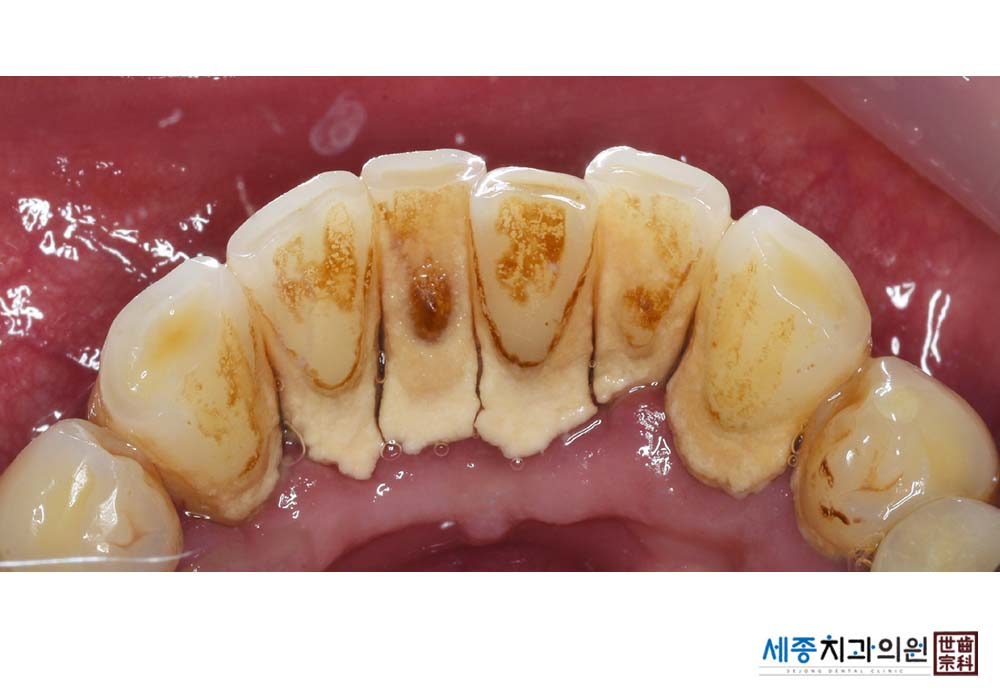

[스케일링] 치주질환 예방 스케일링

치료전 : 2023-02-21

치료후 : 2023-02-21

가글마취&저주파 스켈러를 사용한 스케일링